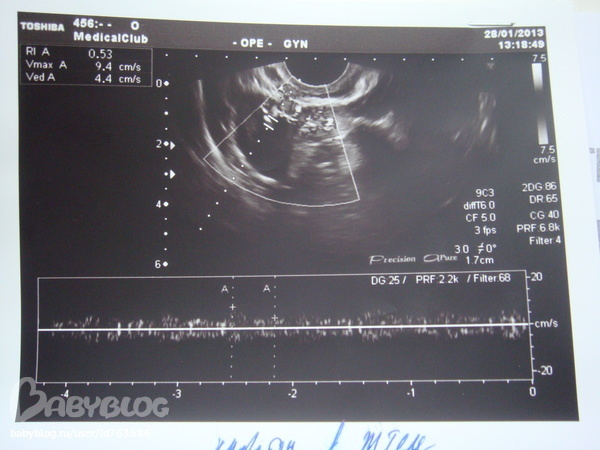

Снижение кровотока в Желтом теле

ФолликулометрияДевочки кто разбирается в узи,написали вчера снижение кровотока в ЖТ и размер 16мм,это плохо или с этим можно жить